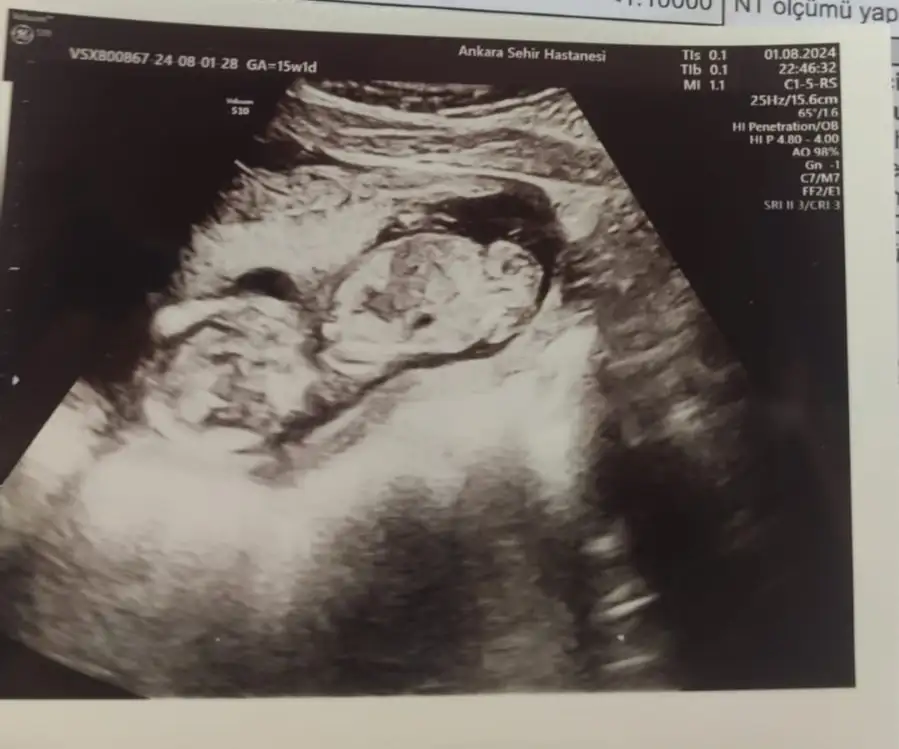

Merhaba öncelikle hayırlı olsun sağlıkla gelsin bebisiniz 😊🙏🏻🧿 bize de 12. Haftada özelde kesin kız dedi doktor dun devlette doktora gittiğimizde henüz göstermiyor dediler bizimde değişir mi sizin gibi fotoğrafları ekliyorum ilk fotograf 12. Hafta bacak arası fotoğrafı ikinci fotoğraf 15+1 yorum yapabilecek olan varsa çok sevinirim